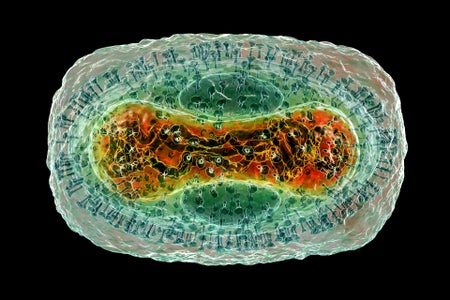

Why is Monkeypox Evolving So Fast?

The virus circulating in the current outbreak has mutated 50 times in the past four years

What Is Monkeypox, the Virus Infecting People in the U.S. and Europe?

A microbiologist explains what is known about this smallpox cousin